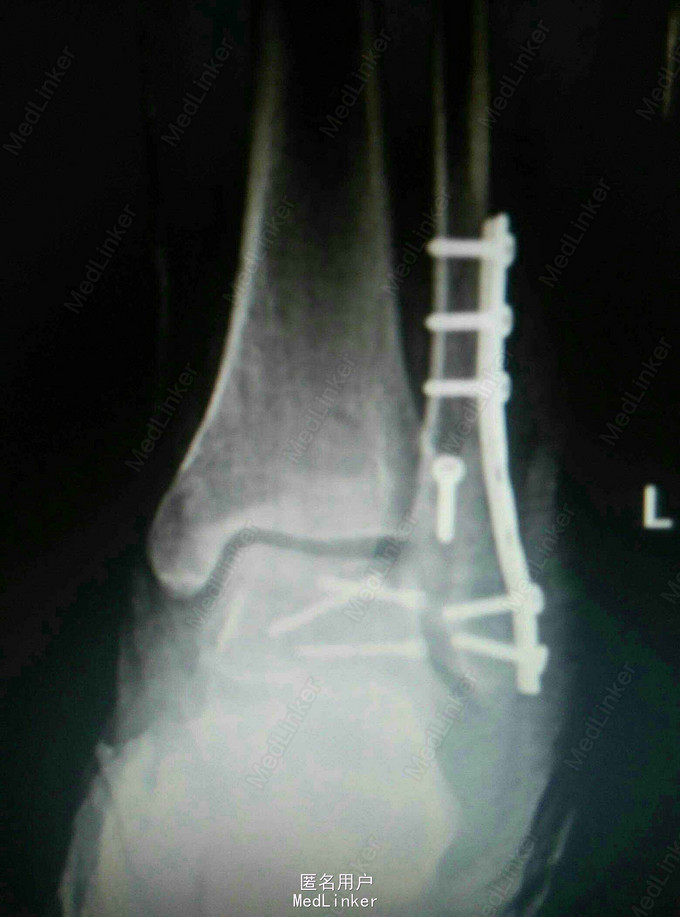

行外踝截骨入路显露复位螺钉固定术

术后功能好,体表像,复查X线片